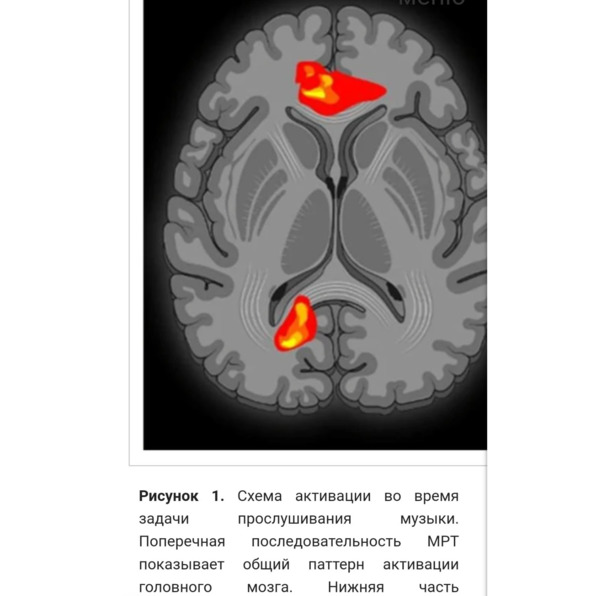

Что происходит при слушании музыки

«При слушании музыки – большая активность в гамма-, бета- и альфа- диапазона. (1) гамма- активность как аффективную реакцию и сознательное распознавание предпочитаемой музыки; (2) бета-активность как оценка темпа предпочитаемой музыки и эмоциональное возбуждение, связанное с предпочтением; (3) альфа- активность как усиление внимания к когнитивным функциям, таким как восстановление памяти; и (4) усиленная синхронизация в альфа- диапазоне у танцоров, обусловленная воображением движений или творческим мышлением в целом. Музыкальная подготовка не оказывает существенного влияния на степень восприятия грува при прослушивании музыки/ритмов с высоким или низким ритмом или шума» (Stupacher et al., 2013, Witek et al., 2014). «Обучение танцам и музыке влияет на слуховую обработку, включая изменения в нейронной активности, связанные с конкретными музыкальными событиями, а также на синхронизацию различных частотных диапазонов мозговых волн (тета, альфа, бета и гамма) на разных электродах на коже головы» («Нейронаука танца…").